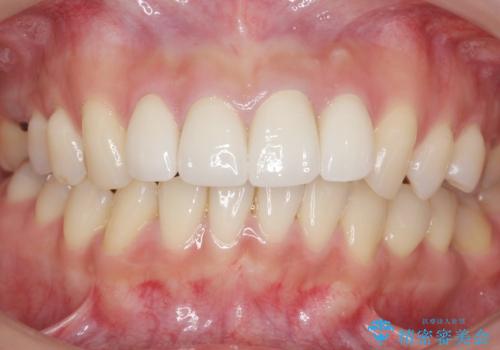

前歯をきれいにしたい 20代女性

- 前歯をきれいにしたいとのご希望により来院された患者様です。

ご希望により、上の前歯4本のセラミッククラウンによる補綴治療を行いました。

綺麗な仕上がりに喜んで頂けました。

患者様のご希望により、クラウン作製前にオフィスホワイトニングを行いました。

今後ホワイトニングを継続し天然歯をより白くしていく予定とのことで、クラウンのお色味は隣在歯よりやや白めにオーダーしております。

クラウンの種類:オールセラミッククラウン スタンダード